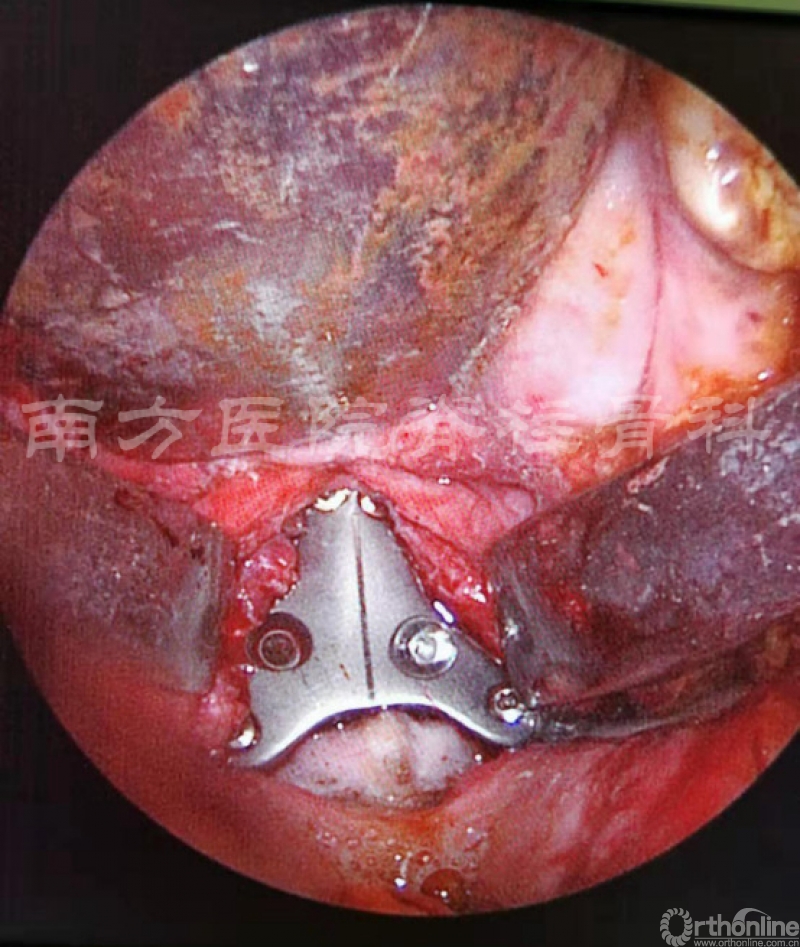

经口腔完成肿瘤切除后3D打印枢椎假体固定

借助于脊柱骨科的“广东省脊柱外科虚拟现实与器械工程技术研究中心”这一技术平台,蒋晖副主任带领的团队独具匠心地提出在鼻内镜辅助下单一前路经口腔切除枢椎肿瘤,并根据切除肿瘤侵犯的范围设计置入3D打印人工椎体,并在人工椎体上设计好颈1-3螺钉的钉道及导航模板,人工椎体内预留植骨通道,从而实现以微侵入的方式通过单一切口切除肿瘤、重建脊柱并达到脊柱稳定性的目标。经过与3D打印公司的反复沟通,历经10余次修改,最终获得了所需要的人工椎体。